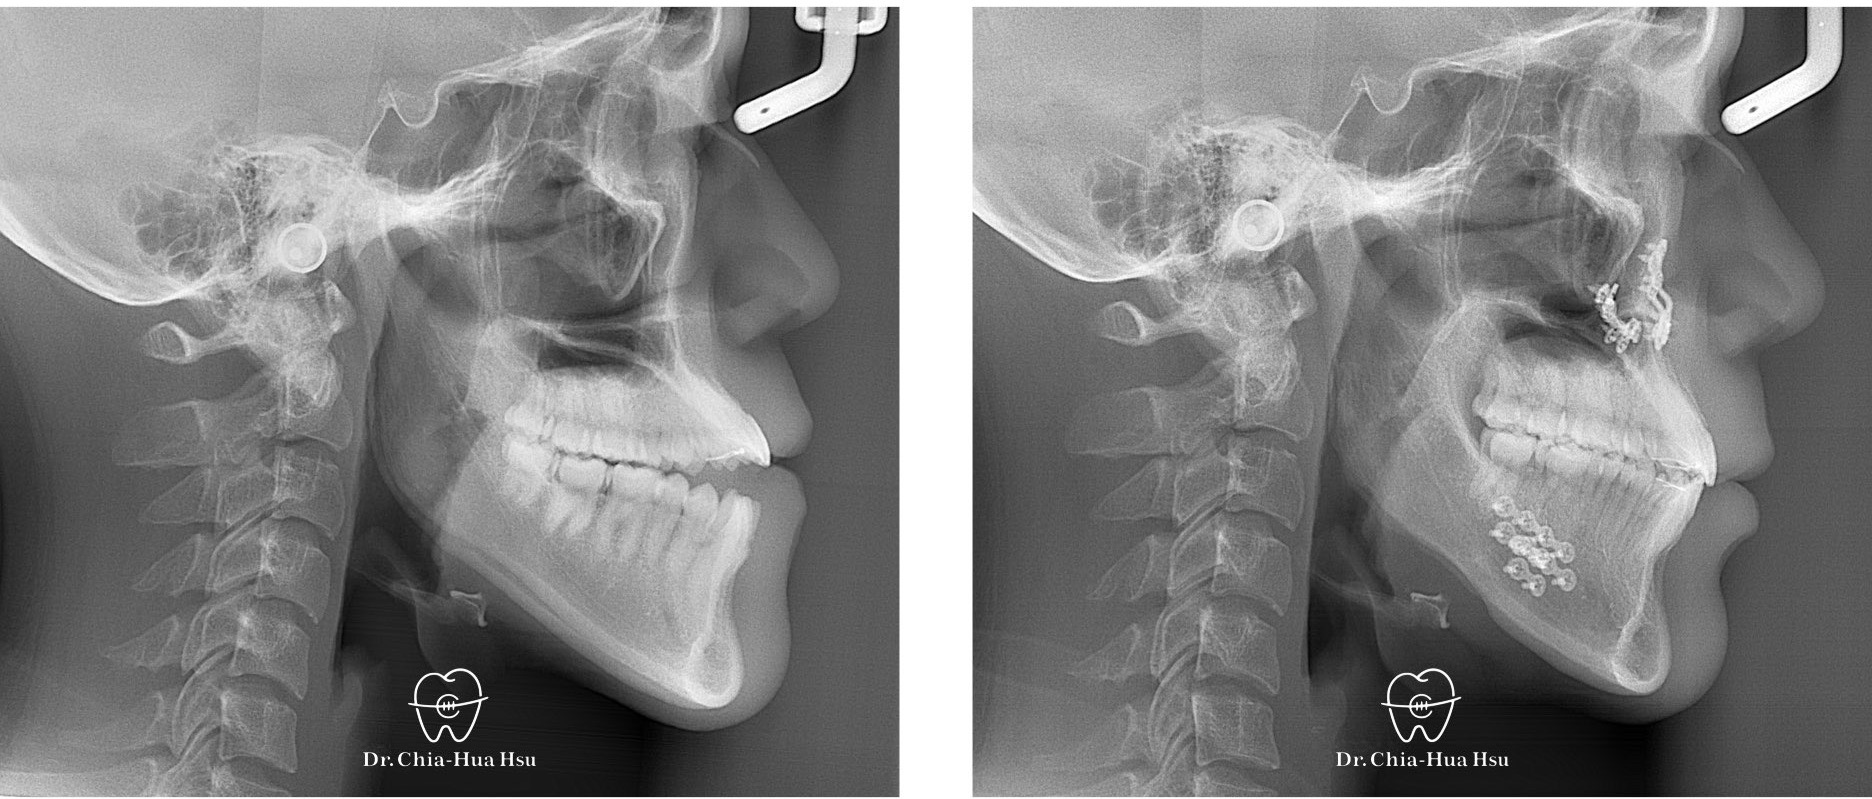

戽斗、開咬、齒列不正

成⼈矯正 | ⾦屬矯正 | 正顎⼿術 | 拔牙治療

• 20多歲的日籍大學生小時候有做過矯正治療,不過下顎骨隨著年紀持續生長,變成戽斗且開咬的樣子。於是,患者接受了矯正合併正顎手術,不但改善外觀,也改善了咬合功能與牙齒排列(患者很開心可以咬斷麵條)。

• 病患主訴:戽斗、前牙開咬。

• 問題分析:患者是標準的骨骼三類咬合(Skeletal Class III),下巴明顯較長,還有上顎牙弓過窄、開咬以及齒列不正。

• 治療方式:使用傳統金屬矯正器,合併正顎手術(雙顎),上顎拔除兩顆小臼齒以利手術方式進行上顎牙弓擴寬。

• 治療時間:1 年 7 個月。

• 治療結果:齒列排齊,咬合功能恢復,外觀更和諧。

治療前

治療後